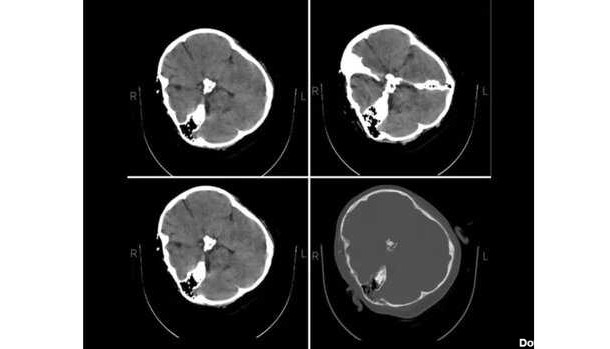

عکس سیتی اسکن بازیکن عربستان

تصویری از جمجه شکستهشده یاسر الشهرانی مدافع تیمملی عربستان نشان میدهد وضعیت شکستگی صورت وی بسیار وخیم است و باید سریعا تحت عملجراحی قرار بگیرد.

یاسر الشهرانی به دلیل مصدومیت شدید در بازی مقابل آرژانتین ادامه جام جهانی ۲۰۲۲ قطر را از دست داد.

در واپسین دقایق دیدار عربستان مقابل آرژانتین، یاسر الشهرانی پس از برخورد با محمد العیوس دچار مصدومیت شدید از ناحیه صورت شد و با برانکارد از زمین بازی بیرون رفت.